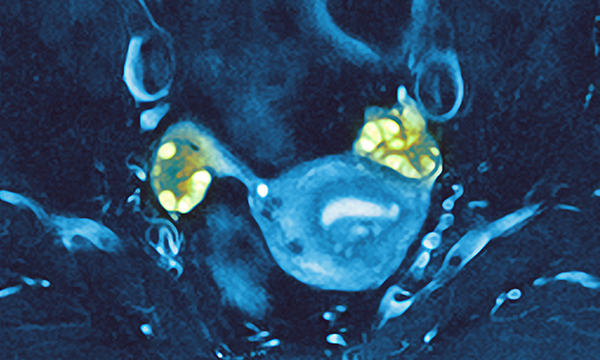

A broadening of the definition of polycystic ovary syndrome has contributed to a steep rise in diagnoses and risks causing fear and anxiety, health experts say.